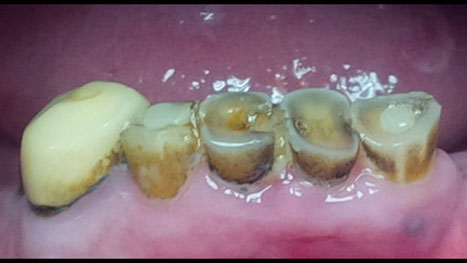

Clinical Uses for Silver Diamine Fluoride

Silver Diamine Fluoride

I first began using silver diamine fluoride (SDF) in my private pediatric dental practice in 2015. Minimally Invasive Dentistry is a topic near and dear to my heart as a mother and advocate for improving children’s oral health and safety. My own daughter having surgery under general anesthesia at just nine months coupled with experiencing … Read more